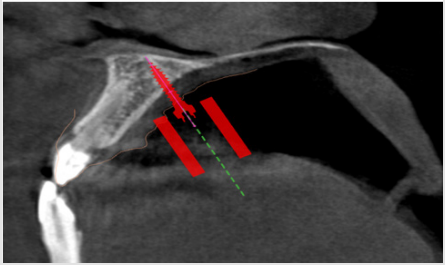

The CBCT showed favorable implant planning positions, with more than half of their length fixed in the bone. Although the left side of the vault was not as thick as theright one, a thin blade of cortical bone remained between the nasal cavity and the mini implant on the left side of the patient’s palate (Figures 5 & 6).

Figure 5a: Virtual planning of the palatal implants insertion. Image of the left mini-implants’ site in sagittal section.

Figure 6: Virtual planning of the palatal implants insertion. Image of the right mini-implant’s site in sagittal section.

The screws were planned to be angled toward the root of the incisor and as perpendicular as possible to the palatal surface for sufficient retention and efficiency [9]. After the acceptance of the digital planning by the medical team, a surgical guide was 3D printed. The Hybrid Maxillary Expander that was sent from the laboratory on a 3D printed cast consisted of two band sone on the second right upper bicuspid and another one on the first left upper molar, a median screw that was linked to the two paramedian mini-implants and two soldered arms that linked the median screw to the bands. The expander was bonded and in the same appointment, the mini implants were put in place using the printed surgical guide under local anesthesia. After the appointment, the patient was trained to activate the appliance twice a day, under a 90 degree turn until the screw reached the end. The patient was also informed about the apparition of a transitory diastema that was the sign that the suture had opened, and the treatment is successful. At the end of the expansion period, the appliance was kept in place for a 3-month period for healing of the mid-palatal suture that will deliver stability and low chance of relapse (Figures 7 & 8).